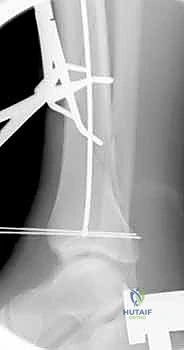

باستخدام جهاز الأشعة السينية المتحرك داخل غرفة العمليات (C-arm Fluoroscopy)، يتم سحب الساق وإعادتها لوضعها التشريحي الصحيح (Reduction) دون فتح منطقة الكسر.

بعد ذلك، يتم إدخال سلك دليلي معدني رفيع داخل القناة النخاعية، يليه استخدام أدوات توسيع دقيقة (Reamers) لتنظيف وتوسيع القناة وتجهيزها لاستقبال المسمار. هذه الخطوة بحد ذاتها تحفز نمو العظم من خلال نشر الخلايا العظمية داخل القناة.

4. إدخال المسمار النخاعي والتثبيت النهائي

يتم تمرير مسمار التيتانيوم بدقة داخل العظم. وبمجرد التأكد من موضعه المثالي بالأشعة، يقوم البروفيسور هطيف بإدخال المسامير التشابكية (Locking Screws) العرضية في أعلى وأسفل المسمار لضمان التثبيت المطلق.